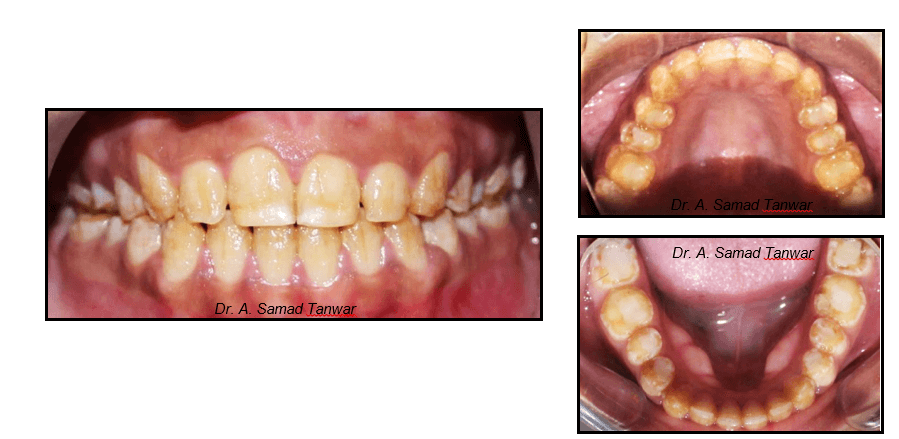

The intraoral photographs of the patient reveals yellowish discolouration of teeth with generalized

On thorough clinical examination it was found that patient has enamel hypoplasia.